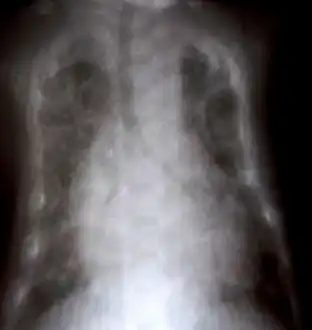

Chest X-ray: Diffuse interstitial syndrome in both lungs